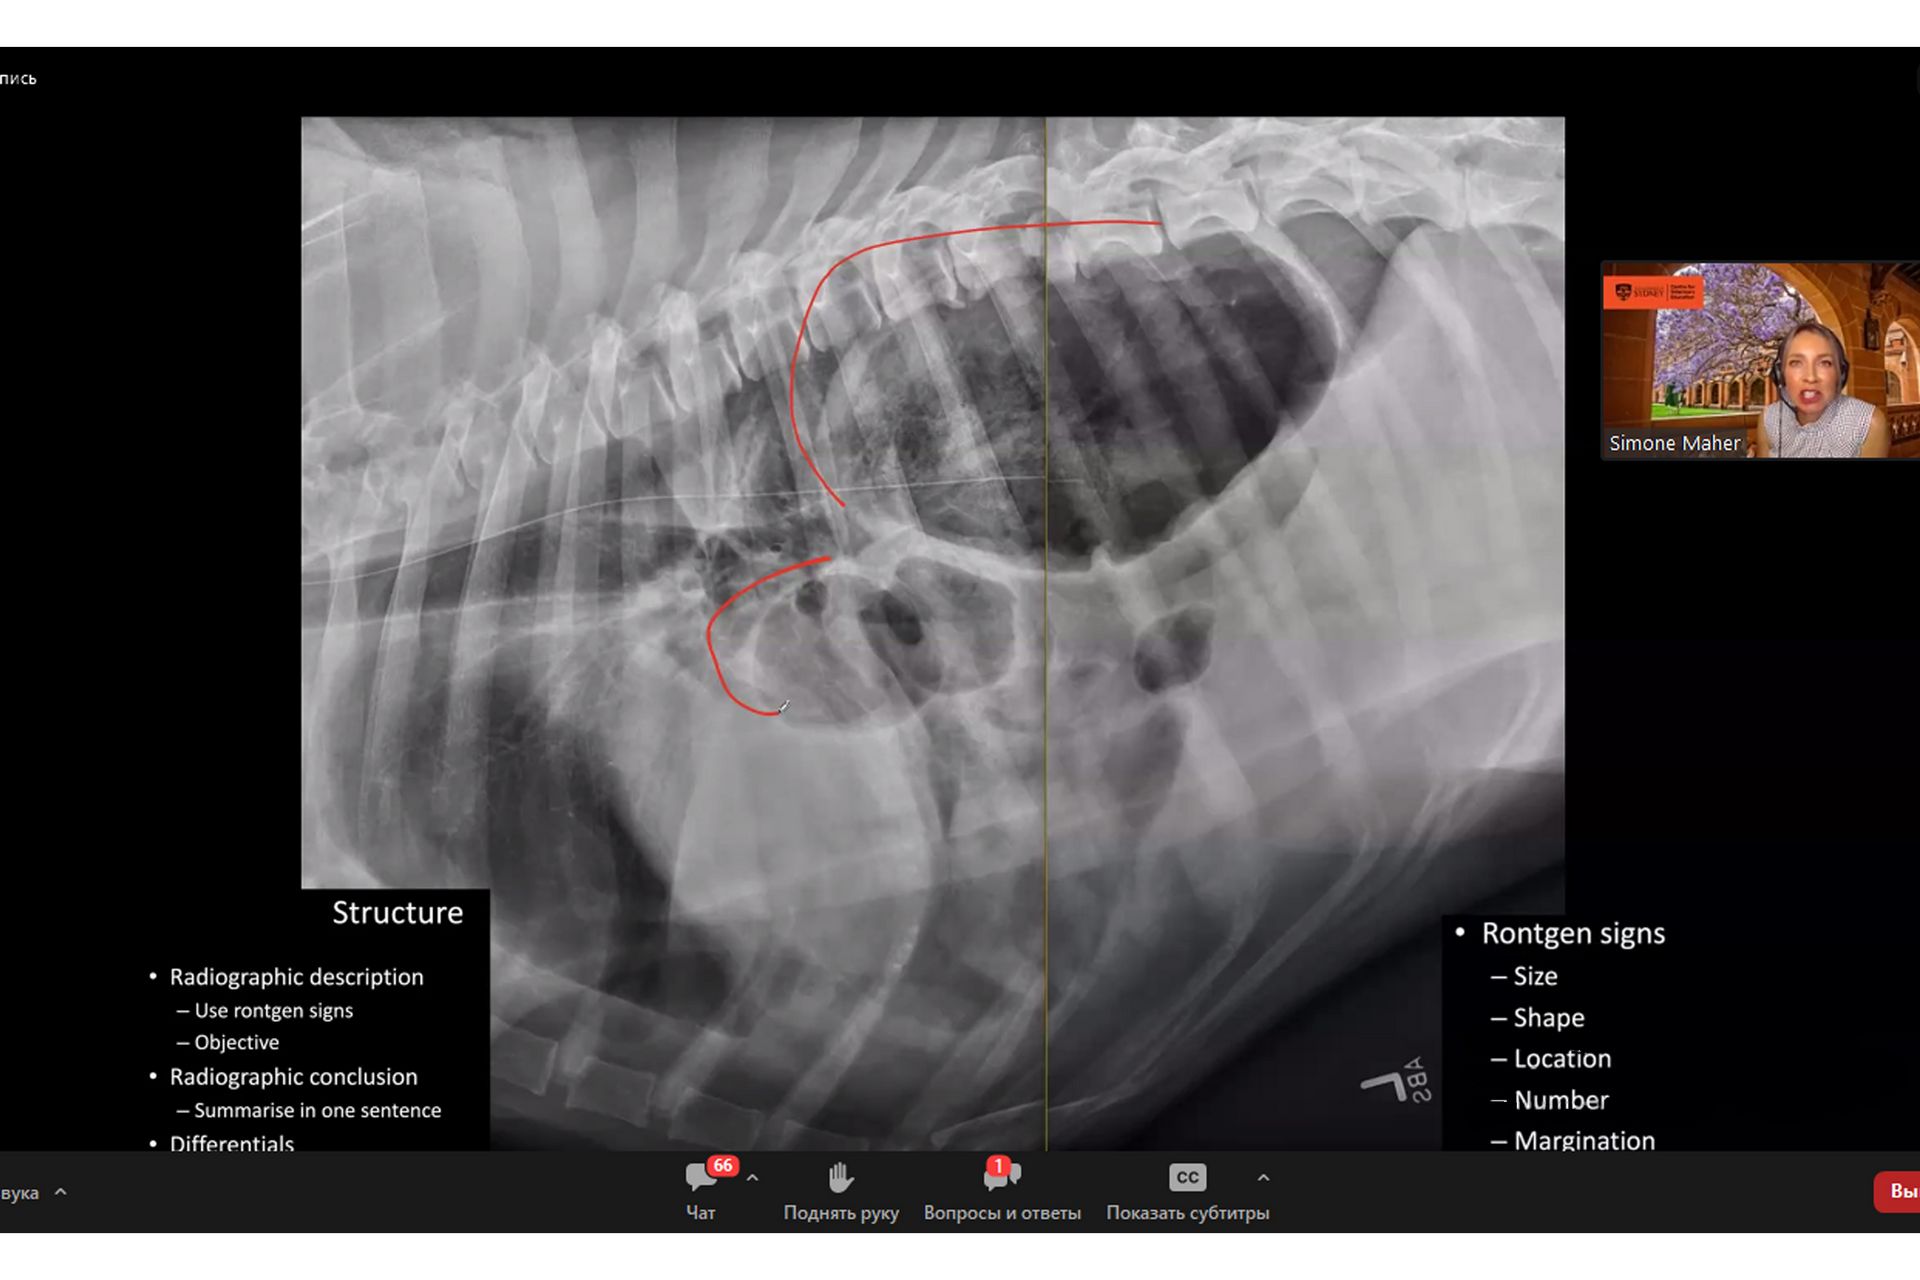

Одна з найпоширеніших діагностичних ветеринарних методик - це рентгенографія. Вона застосовується для вивчення стану тканин і органів при захворюваннях і травмах, а також при первинному профілактичному огляді. З їх допомогою можна отримати детальну візуалізацію різних органів у середині тіла чотирилапого пацієнта. Сучасні  види рентгенівських апаратів для ветеринарії суттєво відрізняються від перших моделей і навіть тих, що застосовувалися кілька десятиліть тому. Завдяки цьому майже виключається ризик опромінення, а швидкість та якість діагностики зростають у рази. Завдяки комп'ютерним технологіям, ветеринарний лікар може обробляти фото на свій розсуд, редагувати контраст і яскравість, збільшувати необхідні ділянки, - все щоб краще бачити патологію.

Пан Ксандер провів майстер – клас з радіології та розповів про основні переваги даного методу дослідження, зокрема те, що сама процедура його проведення проста і не вимагає втручання в організм тварини і, в більшості випадків, не вимагає спеціальної підготовки і може бути виконана безпосередньо на прийомі у ветеринара для встановлення діагнозу, прогнозування перебігу захворювання, визначення його локалізації, спостереження динаміки результатів лікування.

Вебінар надав багато корисної та цікавої інформації для науково-педагогічних працівників, науковців та практикуючих лікарів ветеринарної медицини щодо фізико-технічних основ ветеринарної рентгенології та радіології із описом рентгенотехнічного обладнання ветеринарних рентгенівських кабінетів та додаткових засобів для дослідження тварин. Після завершення вебінару його учасники подякували організаторам та особисто доктору Ксандеру Хейзінгу за надзвичайно корисну й актуальну інформацію, оскільки рентгенографія вважається одним із найбільш інформативних методів сучасної ранньої діагностики хвороб у тварин.